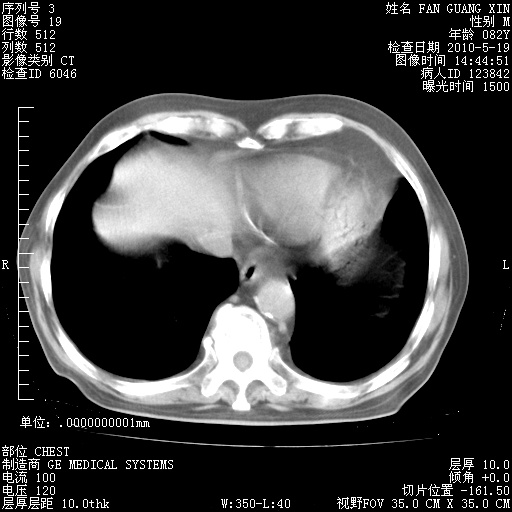

治疗3周后的肺部CT纵隔窗